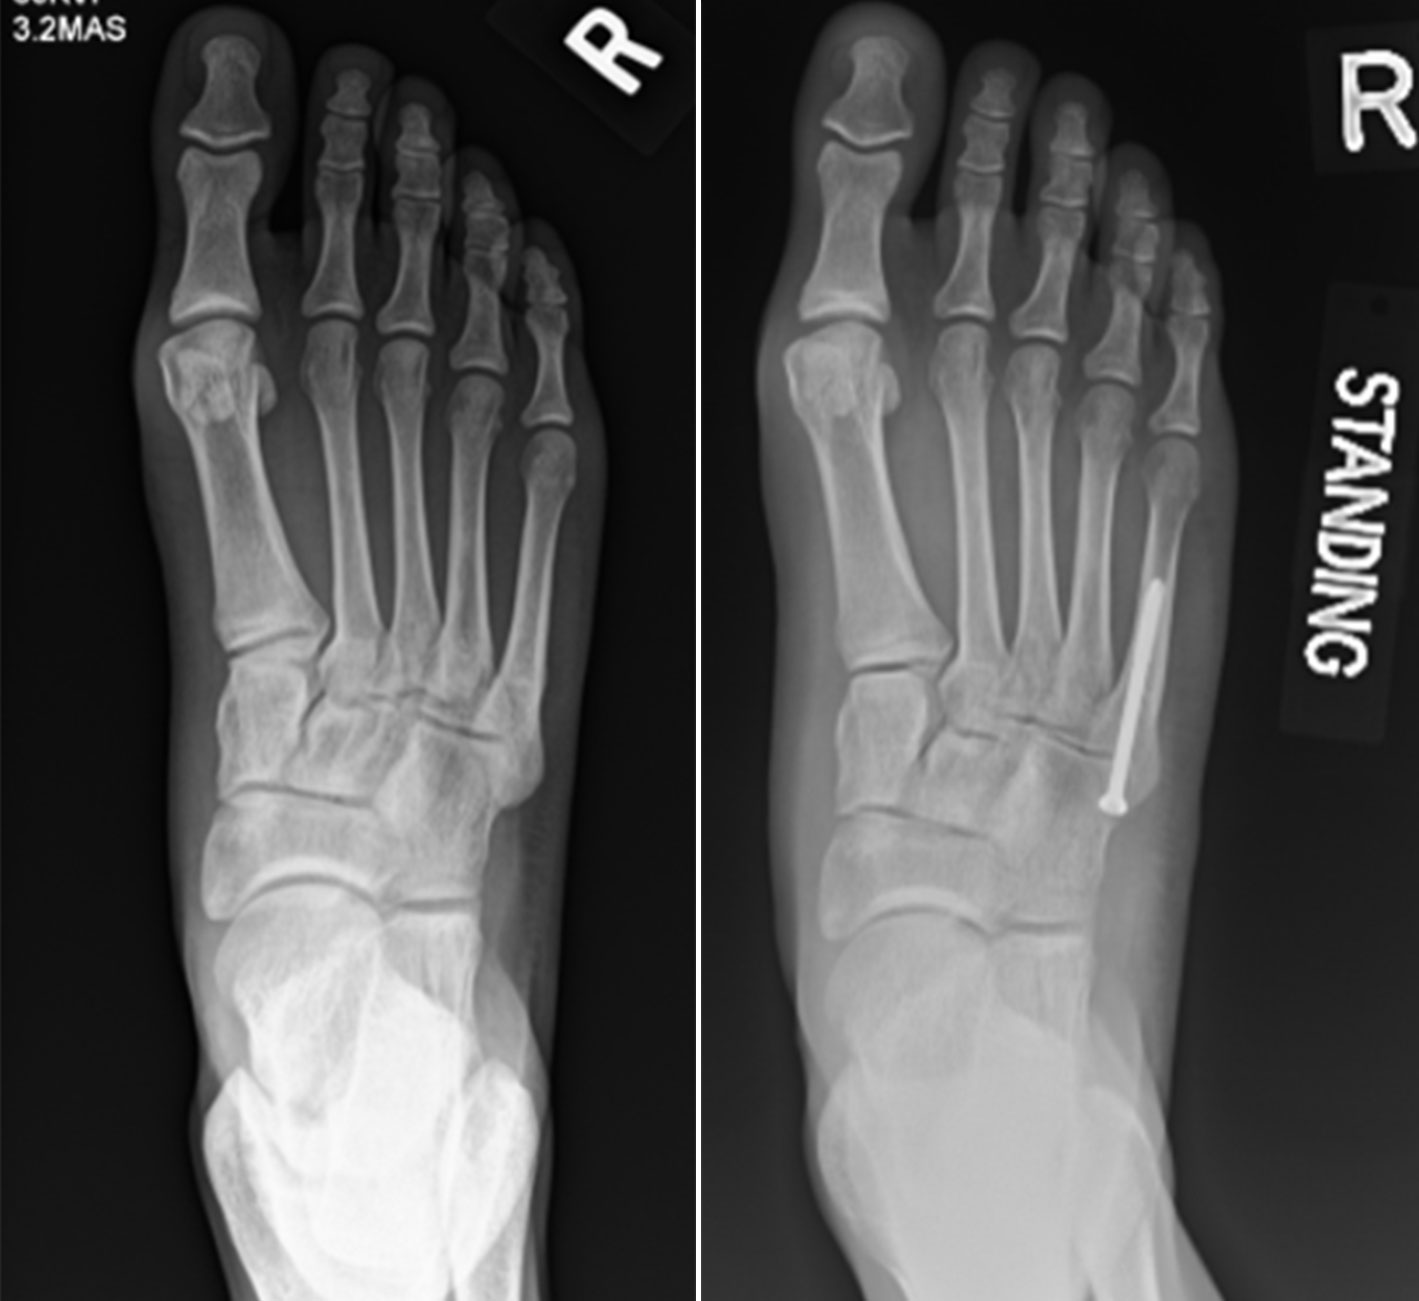

Confused by the difference between a break versus fracture? Both terms describe a broken bone, but they are used interchangeably in medical contexts. Learn the clinical definitions, understand why doctors prefer the term fracture, and discover how these common bone injuries are diagnosed and treated to ensure a fast, effective recovery for your health.

Read full article: Break Versus Fracture